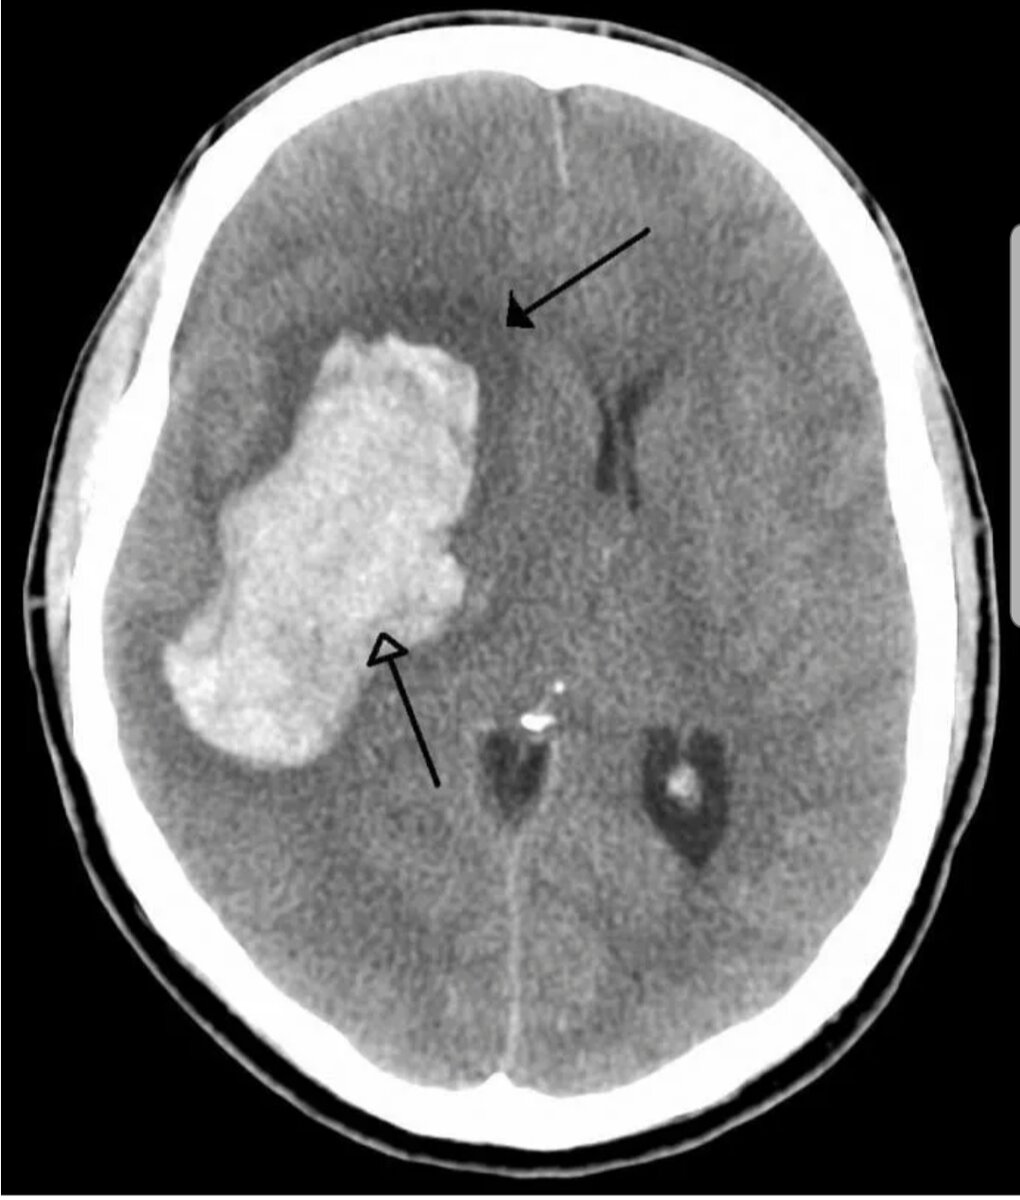

Ниже приведу примеры снимков КТ головного мозга при инсультах.

Геморрагический инсульт (фото из открытых источников)